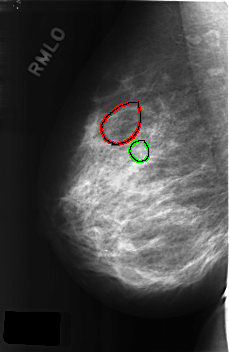

C_0309_1.RIGHT_MLO

RIGHT_MLO LINES 4576 PIXELS_PER_LINE 2976 BITS_PER_PIXEL 12 RESOLUTION 50 OVERLAY

FILE: C_0309_1.RIGHT_MLO.OVERLAY

TOTAL_ABNORMALITIES 2

ABNORMALITY 1

LESION_TYPE CALCIFICATION TYPE PLEOMORPHIC DISTRIBUTION CLUSTERED

ASSESSMENT 5

SUBTLETY 3

PATHOLOGY MALIGNANT

TOTAL_OUTLINES 1

BOUNDARY

ABNORMALITY 2

LESION_TYPE CALCIFICATION TYPE AMORPHOUS DISTRIBUTION CLUSTERED

ASSESSMENT 4

PATHOLOGY BENIGN